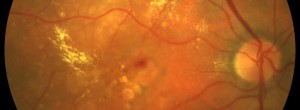

FOVISTA NR: Ensayo clínico para degeneración macular asociada a la edad (DMAE) neovascular

FOVISTA: Ensayo Clínico para pacientes con DMAE neovascular subfoveal

IN-EyE: Ensayo clínico en pacientes naive con neovascularización coroidea secundaria a la DMAE